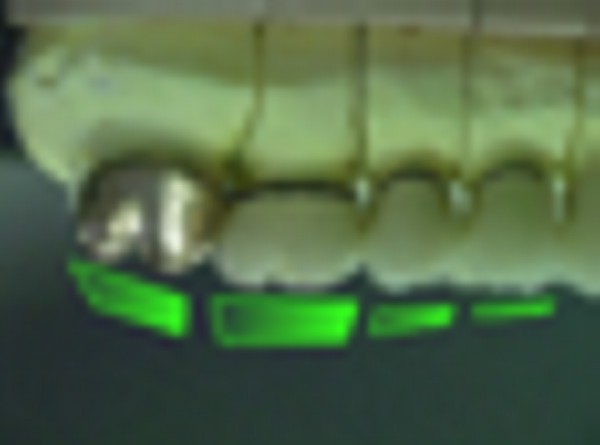

INTRODUCCIÓN El Bruxismo como entidad somática asociada al stress, responde a la mecánica de un Círculo Vicioso Patogénico, que Kawamura describiera hace ya muchos años. FACTOR DESENCADENANTE , que proveen las Interferencias a nivel dentario. En las entregas anteriores se desarrollaron las bases conceptuales de una OCLUSIÓN ORGÁNICA y los efectos de una mayor o menor Desoclusión según la variabilidad de los diferentes Factores Determinantes de la Oclusión. En síntesis; A-La obtención de una Oclusión en Relación Céntrica, nos permite devolver al sistema una elongación muscular fisiológica, sin acortamientos ni estiramientos musculares, sin las consecuentes estimulaciones de los husos neuro musculares, y; una situación estable de la A.T.M. con espacios articulares uniformes. B-El logro de una Guía Anterior que permita desocluir los sectores posteriores durante los movimientos excursivos, nos provée de una segunda y preponderante senda a transitar, que NO estimula por sus contactos excursivos la cincha Pterigo Maseterina, causante de las enormes destrucciones parafuncionales que es frecuente ver en bocas bruxómanas, y la axialización de las fuerzas sobre las piezas posteriores durante el cierre. C-Otorgando como consecuencia, Estabilidad a la tabla premolar-molar, simultaneidad en la recepción de fuerzas durante el cierre(A.T.M. y superficies oclusales). Obtendremos así una Oclusión estable y fisiológica, que no genere el FACTOR DESENCADENANTE del Bruxismo, siempre presente a nivel dentario. INTRODUCTION Bruxism as a somatic entity associated with stress responds to the mechanics of a Pathogenic Vicious Circle, described by Kawamura many years ago. Summarsing: A-Obtaining an oclusion in a Central Relation, allows us to return to the sistem a physiological muscular elongation, without muscular shotthenings or lenghthenings, without the following stimulations of the neuro-muscular huses and a stable situation of the Temporo Mandibular Joint with uniform articular spaces. B-The accomplishment of an Anterior Wide wich may allow disclusive the posterior sectors during the excursives movements, and the axial forces during the mandibular closure. C-Providing as a consecuence, axiality and stability to the posterior sections, responsible of the mandibular closure, through Sttopers, Equalitzers, A, B and C, to obtain a Oclusión Mutuamente Compartida: forces reception during mandibular closure (T.M.J. and Oclusal Surfaces) By this procedure, we should obtain a stable and physiological oclusion, that will not generate the chain link of factors that lead to Bruxism, always present at the dental level. MATERIALES Y MÉTODOS: La funciones articular y muscular, se analizaron mediante Bio Pack, en el pre, en el intra y en el post operatorio. Durante el diagnóstico, tratamiento y remontas, se utilizaron articuladores semi ajustables Wip Mix, totalmente ajustables Artex y arcos faciales correspondientes. El encerado de dianóstico se realizó, mediante la técnica de encerado progresivo de Peter K. Thomas. Los refuerzos a Perno Colado se llevaron a cabo con oro BIODENT YELLOW de ARGEDEN. Los tres juegos de provisionales utilizados, se hicieron con metacrilato termo curado. Las Restauraciones Periféricas Totales, fueron realizadas mediante porcelana CREATION de WILLY GUÉLLER, sobre oro BIODEN YELLOW de ARGEDEN. Los chequeos de los Contactos Interoclusales, se midieron con papeles de articular de 40 y 12 micrones, y mediante el analizador computarizado T-Scan. DESARROLLO Paciente varón de raza blanca, 42 años, complexión robusta y marcada hipertrofia maseterina. Fig.1 Fig.2 Fig.5 Se realiza un análisis pre-operatorio articular y muscular mediante Bio Pack, y oclusal mediante T-Scan, cuyos resultados muestran una evidente hiperactividad muscular en Temporal Anterior y Masetero Derechos, y contactos totalmente anómalos tanto en Oclusión Habitual como en Excéntricas. Fig. 6-7-8-9-10-11 Sensor de ruidos articulares Luego del primer intento de relajación mediante Laminillas de Long (Ref.6),Fig.12, registros y montaje, se observa la aparente presencia de una relación Borde a Borde, que luego se comprobaría que se trataba de una propulsión exagerada de su mandíbula en la búsqueda de contactos efectivos. Fig. 13-14 (Obsérvese el fenómeno de Patterson dado por la exclusiva guía de movimiento de la A.T.M. y la carencia de la Guía Anterior) Se procede a construir un JIG de LUCIA para lograr una desprogramación muscular adecuada, y se le indica permanecer con el colocado durante toda la noche anterior a la consulta, sin contactos dentarios posteriores. Aún en la duda, de que la obtenida sea una posición articular fisiológica, se procede a construir una Placa de Relajación sobre el último montaje obtenido, la que se ajusta cada dos días, y al cabo de tres semanas se procede a un tercer montaje obtenido de la nueva situación posicional. Fig.17-18 Se verifica entonces que estamos en realidad, ante una presunta CLASE II, después de tres métodos diferentes de relajación y transcurridos más de un més de múltiples sesiones para lograr una posición diagnóstica confiable a partir de donde comenzar a trabajar.(O.R.C.) Se adicionan entonces topes (montículos) en las caras oclusales de los primeros molares de la Placa de relajación, transformándola en una Férula Pivotante, de levísima altura, impidiendo el contacto de las demás piezas dentarias a fin de convertir la palanca en una de clase II (fisiológicamente el sistema se mueve según una palanca de clase III), y obtener de esa forma una descompresión de los espacios articulares, ya que si bien la A.T.M. era asintomática, estaba muy claro que la Dimensión Vertical Posterior se presentaba disminuida debido al exagerado desgaste de todos los sectores posteriores, cuya típica forma de «desgaste en olla», se verificaba en el análisis estático de los modelos.( Ref.7) En esa situación se remonta el modelo inferior puesto que el superior no modifica su posición espacial, y se realiza un Encerado de Progresivo Diagnóstico según PKT, previo análisis de los modelos mediante los analizadores de W.McHorris (Ref.8) Fig.18-19-20-21-22-23-24-25-26-27-28-29-30 Fig.18 Fig.22 Fig.23 (Obsérvese, que la Disclusión Propulsiva comienza en los rebordes mesiales del canino, sigue en los rebordes distales del lateral, y finaliza con los rebordes mesiales de los centrales.) Se realizan las endodoncias de toda la boca y se tallan los endodontos para la construcción de Pernos Muñones Colados de oro, los que se realizarán mediante técnica indirecta sobre los modelos :montados según los logros de todos los procedimientos de relajación. Se torna imprescindible la extracción de tres piezas dentarias, para la confección de la Guía Anterior, cuyo alineamiento hubiera sido imposible mediante técnicas reconstructivas ya que la posibilidad ortodóntica no era viable dadas las condiciones de desgaste. Fig.31-32-33-34-35-36-37 (Obsérvese, que desde la configuración de los Pernos Muñones Colados, se determina ya la Alineación Tridimensional que otorgaremos a la Rehabilitación Oral Integral del caso. Se monta entonces el primer juego de Provisionales de acrílico de termo curado, obtenido de la réplica del Encerado de Diagnóstico. Fig.38-39-40-41 (Obsérvese la presencia del ajuste periférico y las disclusiones, tan importantes en las provisorias como en las definitivas ya que del resultado de la etapa de provisionales, dependerá el éxito final.) Se ajustan las Unidades de Oclusión mediante Ajuste Oclusal (según técnica propuesta por la Cátedra de Operatoria Dental II y Prótesis de la Fac. de Odontología, Univ. Bs. As., Prof.Anibal Alonso.) Se deja actuando la nueva situación durante seis meses. Han transcurrido seis meses durante los cuales se instaló un nuevo juego de provisorios con las mismas características del anterior, y clinicamente no se observa hiperactividad muscular, perforaciones de los provisorios, molestias para desmenuzar los alimentos ni síntomas alguno en la A.T.M. NOS ENCONTRAMOS, CON UN SISTEMA EN PAZ A TODOS SUS NIVELES. Se procede entonces a la toma de impresiones definitivas, mediante la técnica de Impresión a Presión Masticatoria, para la confección de las restauraciones permanentes, y los metales se chequean mediante llaves de Duralay, para observar la situación análoga entre laboratorio y clínica.(Corroboración de la Oclusión en Relación Céntrica)Fig.42-43-44 Se prueban los metales y verifica su ajuste periférico. (Obsérvese que también en los metales sub porcelana se siguen las formas de las Preparaciones Funcionales, permitiendo de esta manera un perfecto bizcochado de la porcelana supra metal.) Realizada la Guía Anterior, Determinante Oclusal Primario y Anterior en el laboratorio, se prueban en boca sus características estáticas: Altura Funcional, Ángulo de la Disclusión y Punto de Acoplamiento, como así las dinámicas: Laterotrusión Derecha e Izquierda y Propulsión. En este estado las cosas, tenemos al sistema circunscripto tanto estática, como dinámicamente, por el gobierno de dos comandos, ya en Oclusión en Relación Céntrica, como en las Transtrusiones: Sabemos que todo lo que construyamos (tabla premolar-molar), entre estos dos comandos rectores del movimiento, partirán del mismo punto y volverán a el, transitando el recorrido impuesto por los mismos. Se construyen entonces en el laboratorio, las unidades de oclusión de premolares y molares, siendo las correspondientes a los cuatro últimos molares, con oclusal en oro, como un elemento de detención del cierre más poderoso que la porcelana.47-48-49-50-51 Se prueban en boca la Curva de Wilson, la Curva de Spee, la Alineación Tridimensional, los Espacios Uniformes Disclusivos, la Dirección de los Surcos de T, nT, y P, y los Puntos Interoclusales de Contacto. En laboratorio se retocan entonces los Puntos Interoclusales de contacto, acercando los mismo a la mejor posición ideal lograble, y luego de una nueva prueba en boca, se glacéan las piezas y se instalan en forma provisional durante 24 hs. Verificada la eficacia de las formas (FORMA=FUNCIÓN), se procede a constatar la eficiencia de la dinámica trayectorial y se cementan con cemento de fosfato mediante la técnica de cementado alterno. Fig.54-55-56-57-58-59-60-61-62-63-64-65-66-67-68-69. Fig.54 Fig.55 Curva de Wilson y Alineación Tridimensional en molares y premolares sup. Der. Fig.56 Fig.57 idem inferiores derechos Fig.58 Fig.59 Idem superiores izquierdos CONTACTOS INTEROCLUSALES SUPERIORES CONTACTOS INTEROCLUSALES INFERIORES Transcurrido un mes de instalada la Rehabilitación, se lleva a cabo un nuevo estudio, post operatorio con Bio Pack y Tscan. CONCLUSIONES : I-El paciente realiza una apertura bucal de 45mm sin forzamientos siguiendo una misma línea de apertura sin desvíos. II-Las disclusiones en laterotrusión se llevan a cabo mediante un recorrido lineal sobre los rebordes medios de ambos caninos superiores, creando un fenómeno de Luce con espacios uniformes en ambos lados. III-La disclusión en propulsión se manifiesta comenzando en los rebordes mesiales de ambos caninos, siguiendo por los rebordes distales de laterales y terminando en los rebordes mesiales de ambos centrales, dando lugar a un fenómeno de Christensen con espacios uniformes de ambos lados. IV-Los contactos interoclusales son suficientes, simultáneos y tripódicos logrando la estabilidad en ambos planos del espacio tanto de las piezas individuales como en conjunto, sin contactos deflectivos. V-Realizado un nuevo montaje de la boca terminada, corroboramos como estable la Oclusión en Relación Céntrica. VI-No existen movilidades dentarias y los tejidos periodontales y gingivales se encuentran estabilizados. VII-No existen ruidos articulares. VIII-El resultado post operatorio Bio Pack de la dinámica mandibular, muestra una sustancial mejora de los movimientos en los tres planos del espacio. IX-Electromiográficamente, se observan contracciones musculares dentro de los rangos de normalidad, persistiendo un rango ligeramente elevado en temporal anterior y masetero del lado derecho, presumiblemente debido a la hipertrofia que dicho paciente traía, y mostraba en el estudio pre-operatorio. COMPARACIONES PRE, INTRA Y POST OPERATORIAS Sonografía de la ATM: Tanto en el examen pre como post operatorio no se observaron ruidos de ningún tipo, coincidiendo con la exploración clínica pre auricular e intra auricular. Electromiografía: La electromiografía en reposo, muestra bien a las claras la presencia de músculos hipertónicos durante el estudio pre operatorio, fundamentalmente del grupo Temporal Anterior y Digástricos, estando el Masetero izquierdo ligeramente por encima de su rango normal como así también ambos Esternocleidomastoideos. Durante el estudio post operatorio, se verifica el estado tónico de todos los grupos musculares, persistiendo una ligera hipertonicidad de rango levemente por encima de lo fisiológico, en el Temporal Anterior Derecho y Digástrico Derecho. PRE OPERATORIO POST OPERATORIO Temporal Ant. Der. 4.4 2.8 Temporal Ant. Izq. 6.2 1.1 Masetero Der. 1.2 0.5 Masetero Izq. 1.5 0.8 Est.Cleid.Mast. Der. 1.6 0.3 Est.Cleid.Mast. Izq. 2.1 0.2 Digástrico Der. 1.7 2.9 Digástrico Izq. 1.6 0.7 (La unidad de medida utilizada es el microvoltio ) Dinámica mandibular: Durante el Pre Operatorio, en el Plano Sagital, tanto la Apertura como el Cierre lento, se manifiesta mediante una acentuada tendencia a propulsar la mandibula. Durante el Post Operatorio, la tendencia hacia la derecha de estos dos últimos planos se mantiene, mientras que en Plano Sagital, la propulsión inicial no se produce, asemejándose el movimiento a la primera fase del Bicuspóide de Posselt. El Análisis de la Dinámica realizado durante la Masticación (chicle), nos muestra en el Plano Sagital, la propulsión mencionada durante la apertura y cierre lentos durante el estudio Pre Operatorio, se aproxima a la normalidad durante el Intra Operatorio (2º juego de provisionales), y se vuelve a manifestar propulsivo, en el Post Operatorio. En cuanto al Plano Frontal, durante el Pre Op. , ofrece un Ciclo Masticatorio(recordar la forma de «gota de agua») para el lado izq., con componentes derechos e izquierdos alternos, que se aproximan paulatinamente al Ciclo Masticatorio Normal, durante el Intra y Post Operatorio. El Plano horizontal, confirma las afirmaciones anteriores durante los tres períodos de estudio. ANÁLISIS MEDIANTE TSCAN 1-Bio Pack Bio Research Associates,Inc Distrib.UEDA S.A. 2-Wip Mix-Artex 3-Au:89% / Pt:6% /Elementos complementarios:5% 4-Idem ref.3 5-Tscan TekSkan,Inc Distrib.UEDA S.A. 6-Mc Horris.Cátedra de Operatoria Dental II y Prótesis. 7-Alonso.Cátedra de Operatoria Dental II y prótesis. 8-Mc.Horris. Analizadores de Guía Anterior. BIBLIOGRAFÍA: 1-Esquemas de las dos primeras entregas, tomadas del libro:»Oclusión Orgánica…un camino hacia la Rehabilitación Oral» 2-Oclusión y Diagnóstico en Rehabilitación Oral. 3-Anatomia Odontológica. 4-A contribution to the study of the movementes of the mandible. 5-Celenza F.W, Nadeskin J.F.,Oclusión.Situación actual. 6-D´Amico 7-Dawson P.E. 8-Huffman -Regenos. 9-Hobo S.-Takayama H.A. 10-Lucia V.O 11-Mc Horris. 12-Mc Horris. 13-Posselt U. 14-Stuart C. 15-Vartan Veshnilian AGRADECIMIENTOS: La Rehabilitación Oral, especialidad donde se hace imprescindible el manejo y concurrencia de todas las especialidades dentales en su desarrollo más depurado, no tendría razón de ser, sin la más estrecha colaboración de una técnica para- médica con detalles de excelencia. Sr. Pedro Colomina: muchas gracias. Pedro Colomina. – Titulado especialista en prótesis dental en la escuela Ramon y Cajal de Barcelona 1988

Al cabo de los mismos se realiza una nueva comprobación del estado articular y muscular mediante Bio Pack y un chequeo oclusal mediante T-Scan, donde se observan una evidente mejoría de la musculatura comprometida, de la dinámica mandibular, de la apertura bucal, de los contactos simultáneos de la Oclusión en Relación Céntrica como así de las Excéntricas, y un manifiesto control masticatorio por parte del paciente.

Se confirma nuevamente la centricidad mandibular a través del contacto canino simultaneo, y se toma con la G.A. instalada (comando anterior de la desoclusión), un nuevo registro intermaxilar. Fig.45-46

A.T.M. a nivel posterior, y Guía Anterior a nivel anterior.

Fig.47

Curva Frontal de Wilson

Fig.48

Curva Sagital de Spee